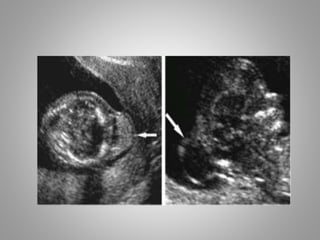

Cephalocoele & Encephalocoele

• Cephalocoele is herniation of intracranial

structures through a defect in cranial vault.

• Meningocoele – when meninges filled with

CSF fluid herniatethrough cranium & when

this meningocoele contains brain tissue, then

it is known as Encephalocoele.

• Encephalocoele herniate mostly through

midline and that too mostly in occipital

region(75%)

• Encephaocoele can herniate and extend in any

direction , i.e. in to nasal cavity , mouth,

sphenoid area, where their identifivation can

be difficult.

• Diffrential diagnosis

1. Cystic Hygroma

2.Hemangioma

3. Scalp Oedema/ cephalohematoma

4. Epidermal or Dermoid cyst.

• Prognosis is poor, mortality in upto 40% cases.